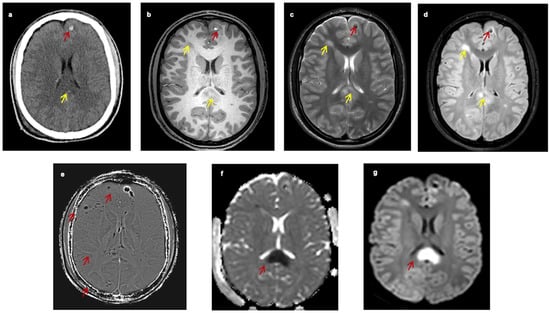

When TAI lesions have hemorrhagic components, techniques that detect blood breakdown products, such as the conventional gradient recalled echo (GRE)-T2* and the advanced SWI (Figure 1e and Figure 2), are preferred. The SWI enhances the contrast of GRE-T2* sequences by combining T2*-magnitude and phase images [25]. Hence, the SWI can detect smaller lesions. In a study of seven young patients with TAI, Tong et al. found that SWI could detect ten times more hemorrhagic lesions than GRE-T2* (1038 vs. 162) [25]. In a larger study including 40 young patients, it was found that the number and volume of hemorrhagic lesions depicted in SWI significantly correlated with patients’ functional outcomes [26]. However, these techniques can only distinguish TAI lesions in the sub-acute or chronic phase [25] because they detect blood breakdown products and hence can mainly support the diagnosis of TAI in cases of diagnostic doubt.

Figure 2. MRI of a 17-Year-old male with traumatic axonal injury, three days post traumatic brain injury (unpublished data), axial plane, SWI sequence shows multiple “dark spots’’ suggestive of haemorrhagic lesions mainly located in the gray–white matter junction of the right temporal, the fronto-occipital lobes and the right side of the splenium of corpus callosum, the midbrain and the left basal ganglia (red arrow). Key: MRI, magnetic resonance imaging; SWI, susceptibility weighted images.